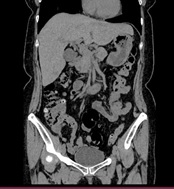

単純CT画像          造影CT画像          MPR画像